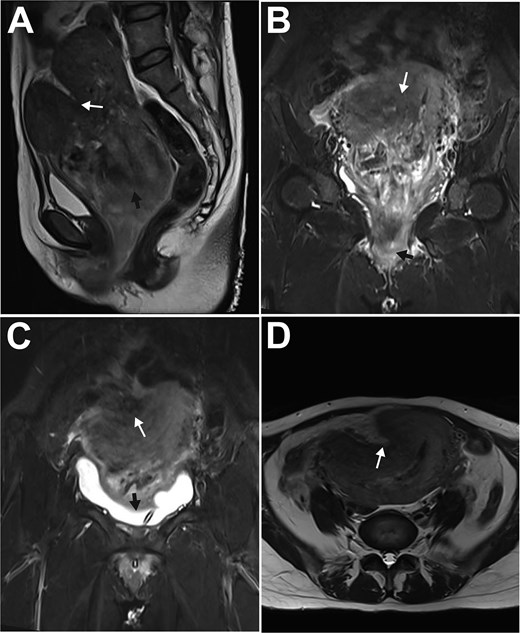

On physical examination, she was afebrile (36.6°C) but tachycardic (117 bpm). Her pre-pregnancy BMI was 17.6 kg/m2 (height 165 cm, weight 48 kg). A dark red, tongue-shaped mass (3 × 3 × 5 cm) protruded from the vaginal introitus, with a larger firm mass (7 × 8 × 9 cm) palpable inside the vagina. The cervix was palpable around the mass; the uterus was anteverted, equivalent in size to a 12-week gestation, mobile, and non-tender. Pelvic magnetic resonance imaging (MRI) confirmed a fundal myometrial indentation, an 86 × 82 × 105 mm heterogeneous intrauterine mass (suggestive of a degenerated submucosal myoma), and a mass extending from the cervical os to the introitus (Fig. 1). Admission diagnoses were: 1) Subacute uterine inversion (Grade I); 2) Prolapsed large submucosal myoma; and 3) Puerperal infection.

MRI features of subacute uterine inversion secondary to a large uterine myoma. A: Paramedian sagittal T2-weighted turbo spin-echo image showed a lobulated fundal depression (white arrow) and the underlying uterine myoma (black arrow); B: Paramedian sagittal T2-weighted turbo inversion recovery magnitude (TIRM) image demonstrated the myoma prolapsing from the uterine cavity into the vagina (white arrow), with a portion extending through the introitus (black arrow); C: Coronal T1-weighted image revealed the myometrial indentation (white arrow) and the compressed urinary bladder (black arrow); D: Axial T2-weighted turbo spin-echo image showed the myometrial depression (white arrow) on the right anterofundal wall.

This subacute presentation on postpartum day 19, marked by less severe hemorrhage possibly from partial endometrial repair, featured the characteristic triad of abdominal pain, mass prolapse, and urinary obstruction. MRI was crucial for diagnosis: it confirmed the inversion and delineated the myoma, demonstrating a "V-shaped" fundal indentation on sagittal view [4] and a focal "lobulated" appearance on axial view instead of the classic "bull's-eye" sign [1], which correlated with the surgical finding of a right anterofundal depression.